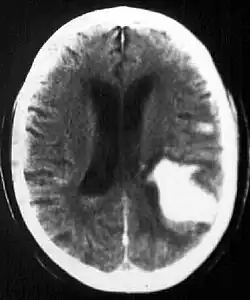

Intraparenchymal hemorrhage

CT-scan of intraparenchymal hemorrhage

Computed tomography (CT scan): A CT scan may be normal if it is done soon after the onset of symptoms. A CT scan is the best test to look for bleeding in or around your brain. In some hospitals, a perfusion CT scan may be done to see where the blood is flowing and not flowing in your brain.